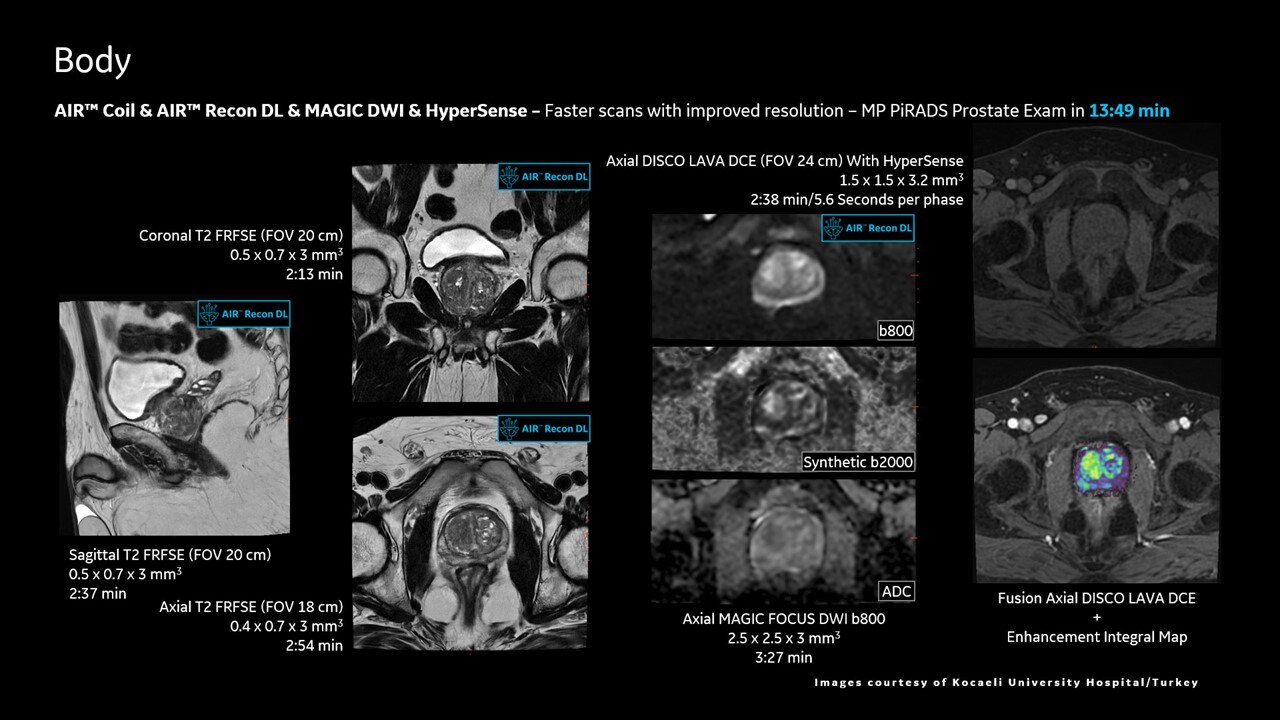

AIR™ Recon DL improves SNR and image sharpness, enabling shorter scan times

Achieve a 25% efficiency gain with Ultra High Efficiency (UHE) gradient system. Fast, clear Total Digital Imaging (TDI) increases SNR by 25%. Improved IQ in 80% of cases without added time. Acquire higher SNR without a time penalty and get images virtually free of artifact with AIR™ Recon DL.***

Attain a 59% productivity gain in exam setup and 37% reduction in table time with AIR Touch™. Five times faster set-up time and four times fewer mouse clicks with AIR x™. Achieve up to a 50% faster acquisition time with AIR™ Recon DL.***